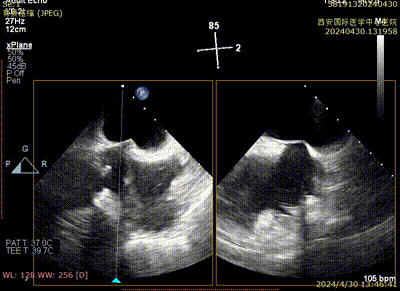

Case 2影像资料

房间隔穿刺

导引鞘系统植入

二尖瓣夹系统瓣上调整

二尖瓣夹系统进入左室

二尖瓣夹捕获瓣叶

二尖瓣夹夹闭

术后二尖瓣反流评估

术后结果